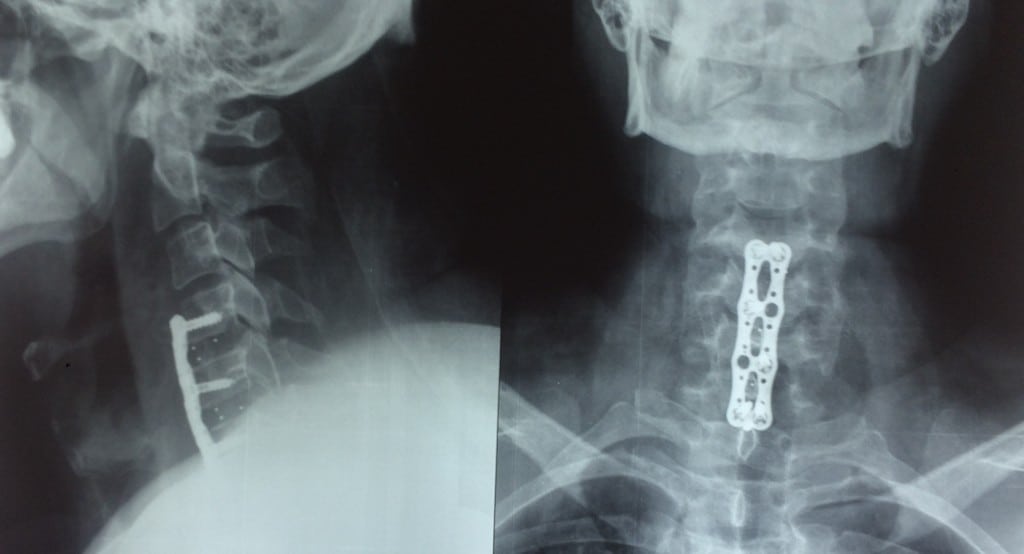

Для диагностирования степени патологии проводится ряд инструментальных исследований, самое информативное из них —рентгенография. Пациентам показаны консультации невролога, кардиолога, эндокринолога. Консервативные методы терапии шейного остеохондроза малоэффективны. Для восстановления утраченных функций, стабилизации позвонков, предупреждения распространения заболевания требуется хирургическая операция.

На рентгенологических изображениях пациентов с этой стадией заболевания заметны значительные разрушения хрящевых тканей и разрастание костных. Обнаруживаются деструктивные изменения скелетной мускулатуры и иннервирующих их нервов. Восстановить поврежденные структуры шейного отдела позвоночника консервативной терапией невозможно. Безрезультативным окажется применение физиотерапевтических мероприятий, лечебной физкультуры, массажа и тем более народных средств. Лечение шейного остеохондроза 3 степени начинается со снижения выраженности симптоматики. Для устранения болей пациентам назначаются следующие препараты: